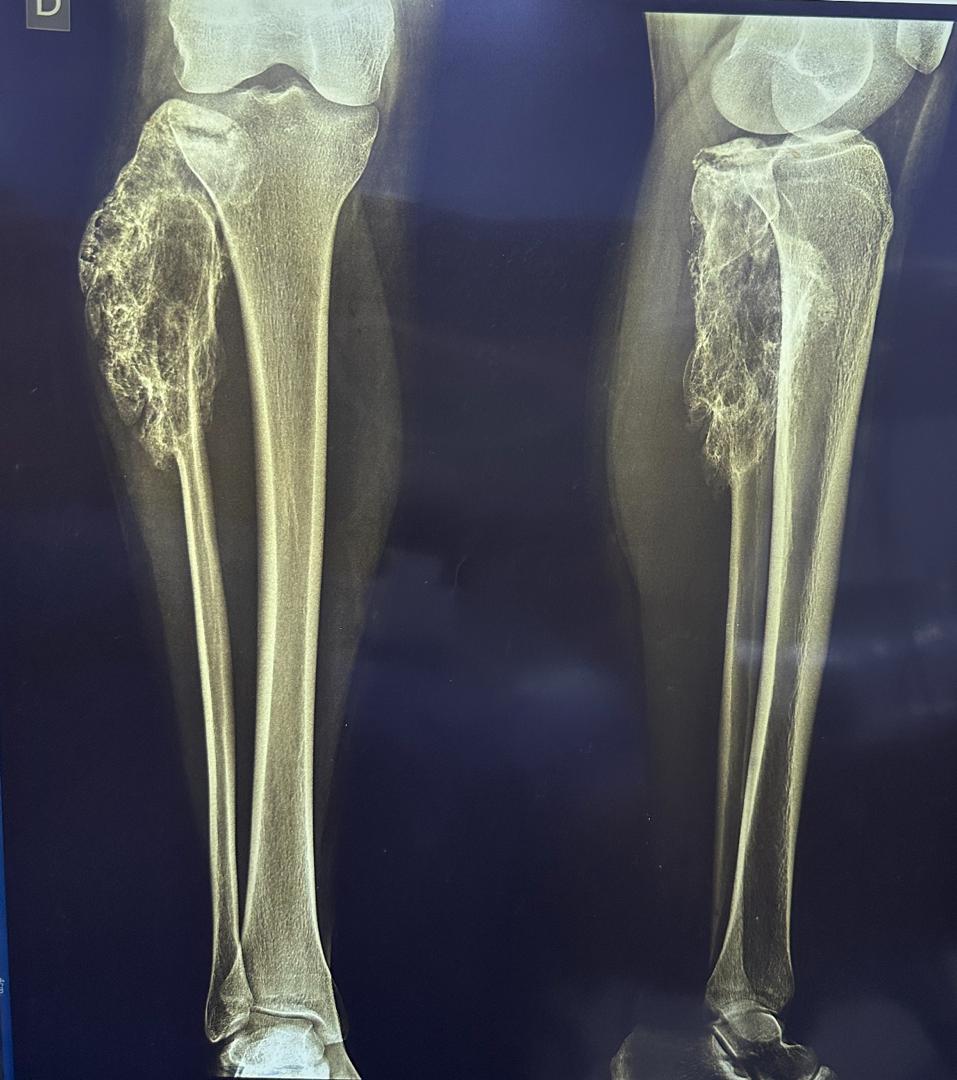

Les signes et symptômes du cancer des os commencent souvent dans un os. Ce cancer affecte principalement les os longs des jambes, et parfois ceux des bras. Les symptômes les plus fréquents comprennent :

- Douleur dans les os ou les articulations. La douleur peut apparaître et disparaître au début. Elle peut être confondue avec des douleurs de croissance.

- Gonflement autour d'un os.

Cancer osseux primitif : chirurgie

- Chirurgie conservatrice : Retirer la tumeur sans amputer le membre.

- Amputation : Retirer un membre si nécessaire pour éviter la propagation.